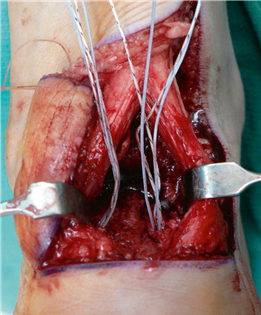

To achieve multiplanar correction, the surgeon must address the sagittal, coronal, and transverse planes. The first metatarsal is plantarflexed to restore the longitudinal arch, rotated out of pronation to realign the sesamoids, and translated laterally to close the IMA. Subchondral drilling or feathering is performed to optimize the biological environment for fusion. Fixation is traditionally achieved with two or three crossed solid or cannulated screws (typically 3.5mm or 4.0mm). Recently, plantar or medial locking plates have gained immense popularity due to their superior biomechanical construct, allowing for earlier weight-bearing. Bone graft or orthobiologics may be packed into the arthrodesis site to stimulate osteogenesis.

Clinical & Radiographic Imaging Archive